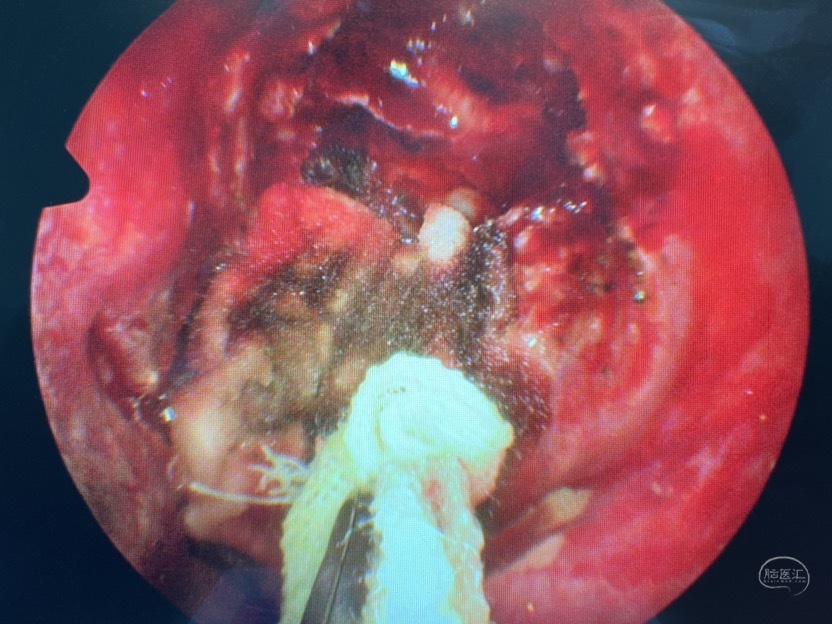

术中证实为蝶窦外侧隐窝的脑膜脑膨出

切除部分膨出脑组织,外侧隐窝因翼突根部的遮挡操作受限